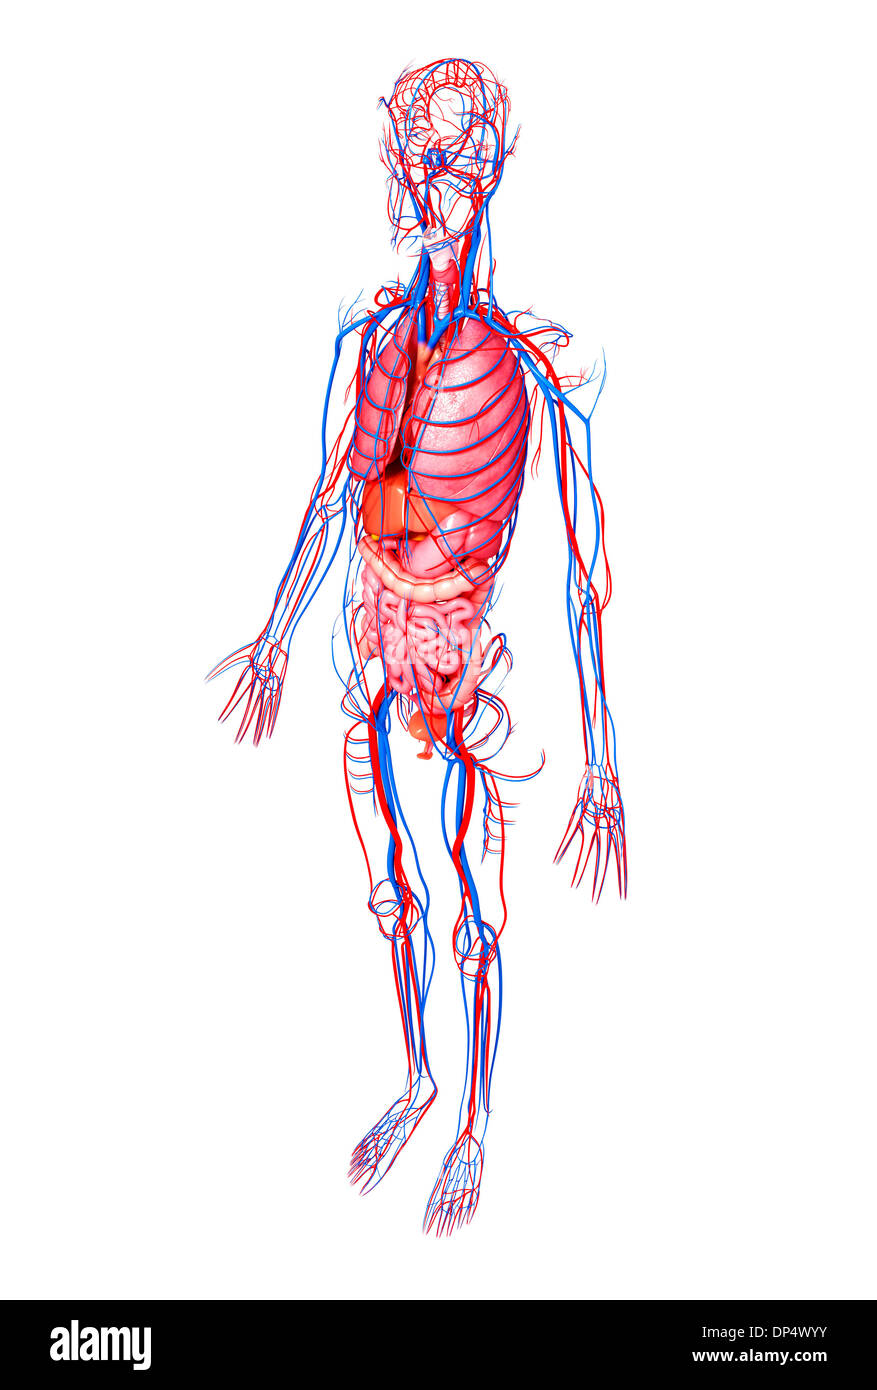

, Artwork Banque D'Imageshttps://www.alamyimages.fr/image-license-details/?v=1https://www.alamyimages.fr/artwork-image65261727.html

, Artwork Banque D'Imageshttps://www.alamyimages.fr/image-license-details/?v=1https://www.alamyimages.fr/artwork-image65261727.htmlRFDP4WYY–, Artwork